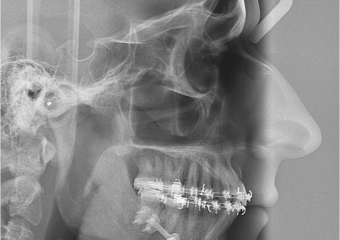

Telerradiografia inicial